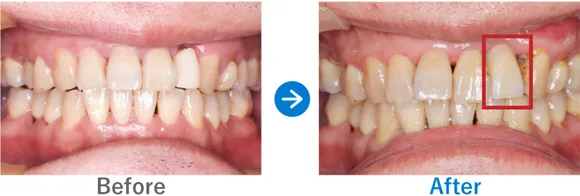

Case11

前歯の差し歯が脱離。インプラントにしてマスクなしで会話がしたい!

右上2の差し歯の離脱、根尖の破折

インプラント1本:右上2、抜歯即時埋入

568,700円(内訳:インプラント1本(ストローマン)、ガイド、抜歯即時埋入、骨補填、仮歯、セデーション、保証20年)

来院の背景

歯の根っこの先端部分が破折し、セラミックの差し歯が下がってしまっている状態でした。しっかり噛めないことに加え、前歯なので人目が気になりマスクが欠かせないそう。「マスクなしで会話を楽しみたい」という想いも、インプラントを検討した動機のひとつだそうです。

治療結果

前歯のため、歯のない期間ができないように抜歯即時埋入でインプラント治療を行いました。また、骨の量が少なかったため骨補填も行いました。噛む力が強いため、定期メンテナンスでのフォローアップが必要です。